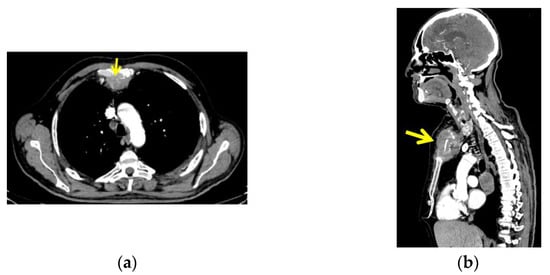

CT with intravenous contrast was performed and showed a sternal tumour of 10 by 11.6 cm at the largest diameter, with no retrosternal extension of the goitre (Figure 4).

Figure 4.

CT with intravenous contrast: sternal tumour of 10 by 11.6 cm; (a) transversal plane; (b) right: sagittal plane.

The CT scan also revealed two tumours at the level of the dorsal upper pulmonary right lobe, measuring 4 by 3 cm and 3.8 by 3 cm, respectively. Multiple mediastinal lymph nodes and a similar lesion at the level of right lateral cerebellum measuring 3.5 by 2.3 cm, and another at the left temporal lobe measuring 1.9 by 2 cm were also detected (metastases).